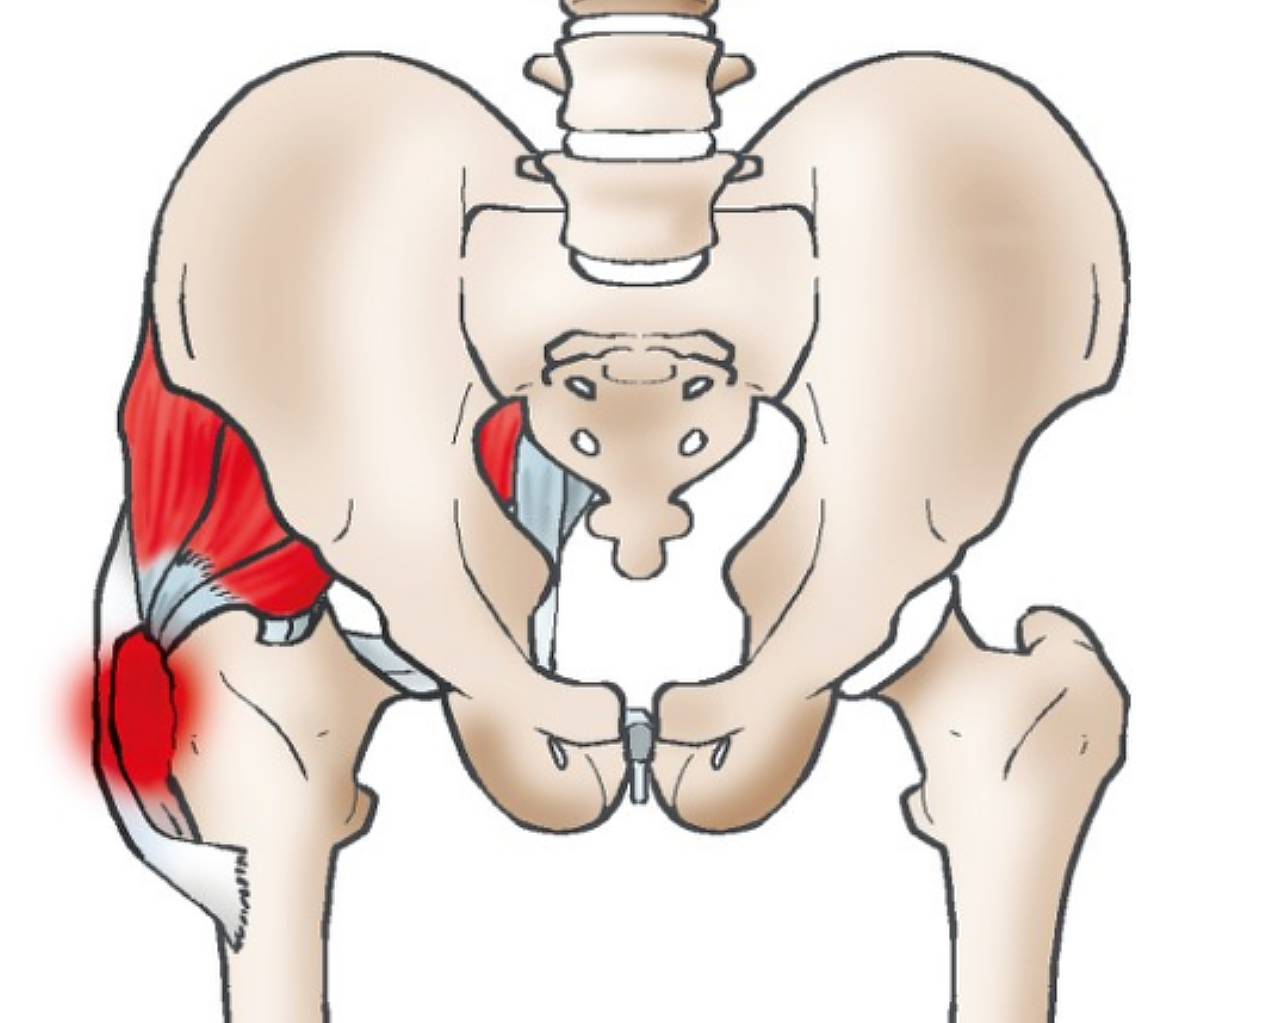

고관절 통증 증상(엉덩관절)은 오른쪽과 왼쪽의 골반과 넙다리뼈가 연결된 관절의 통증을 얘기합니다.고관절은 상체의 하중을 분산시키는 역할을 하며, 걷는 동안 체중의 3배, 달리는 경우 10배에 가까운 하중을 받습니다. 다른 관절과 마찬가지로 감당하기 어려운 충격이나 무게가 가해지면 고관절 통증 증상이 발생합니다. 퇴행성 고관절염, 대퇴골 골절, 대퇴골두 무혈성 괴사, 선천성 고관절 탈구 등이 대표적인 고관절 통증 질환입니다.

고관절은 골반 뼈 속에 공처럼 생긴 대퇴골의 골두가 맞물린 관절입니다. 대퇴골두는 다른 부위에 비해 혈액 순환 장애가 쉽게 올 수 있으며, 혈액 순환 장애는 대퇴골두 무혈성 괴사를 유발합니다. 뼈가 썩으면 몸의 하중을 정상적으로 견디지 못해 미세구조에 골절이 생기고, 심각한 통증이 발생합니다.

고관절 질환은 대부분 초기에는 통증이 나타나지 않거나, 통증이 적어 방치하기 쉽습니다. 평소 걷는 동안 불편함을 느끼고, 만성적이라면 언제부터 통증이 시작됐는지 정확히 기억하지 못합니다. 고관절 통증 증상은 위치상 발견이 어렵고 골반과 비슷한 위치에 있어, 골반 통증으로 오인하는 경우도 많습니다. 질환이 점점 진행되면서 사타구니나 둔부에 통증이 나타났습니다. 심한 경우에는 휴식을 취하고 있을 때도 통증을 호소하게 됩니다.

고관절 통증 증상은 주로 걸을 때 고관절이 위치한 사타구니 쪽에 나타나지만 사타구니는 물론, 고관절 통증 증상 등 신경줄기에 의해 연결된 무릎이나 허벅지 앞쪽까지 통증이 있습니다.